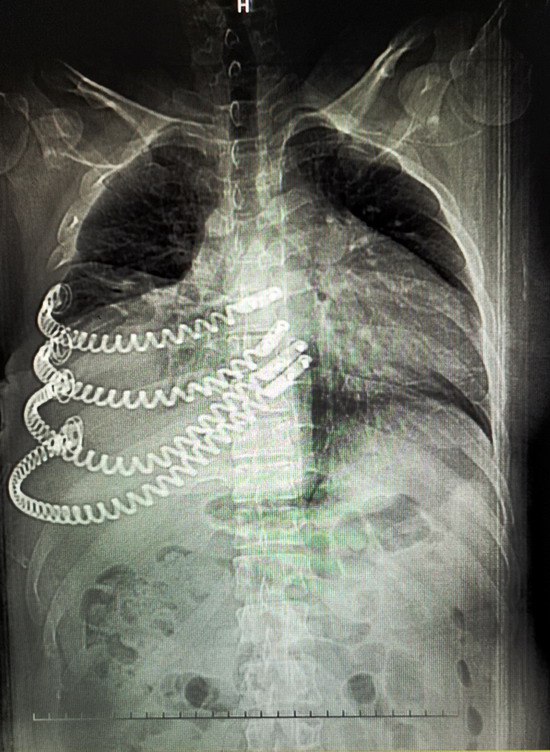

经专家的推荐,家人带着王某来到唐都医院胸腔外科就诊,CT检查显示右前胸壁肿瘤45×35厘米,穿刺活检结果为肋软骨源性恶性肿瘤。由于患者的软骨肉瘤恶性程度高,对放、化疗都不敏感,且易复发,手术切除是首选方案。此外,考虑到患者要切除五根肋骨,术后右前胸壁缺损大,医生决定采用3D打印技术,为王某进行胸廓重建。

2019年10月,王某来到了江苏省东台市某医院做了胸部CT检查。检查结果显示:王某右侧胸壁长了一个外径约45cmX36cm的巨型肿瘤,其右前肋骨骨质已经遭到破坏,医生考虑是软骨肉瘤。

2019年10月,王某来到了江苏省东台市人民医院,做了胸部CT检查。检查结果显示:王某右侧胸壁长了一个外径约45cmX36cm的巨型肿瘤,其右前肋骨骨质已经遭到破坏,医生考虑是软骨肉瘤。

2019年12月9日,小田来到唐都医院就诊,主管医生杨三虎为小田做了CT检查,显示右前胸壁巨大肿瘤,大小是45cm×35cm,鸡蛋大小的包块已经长成篮球大小的肿瘤,穿刺活检诊断为肋软骨源性恶性肿瘤。